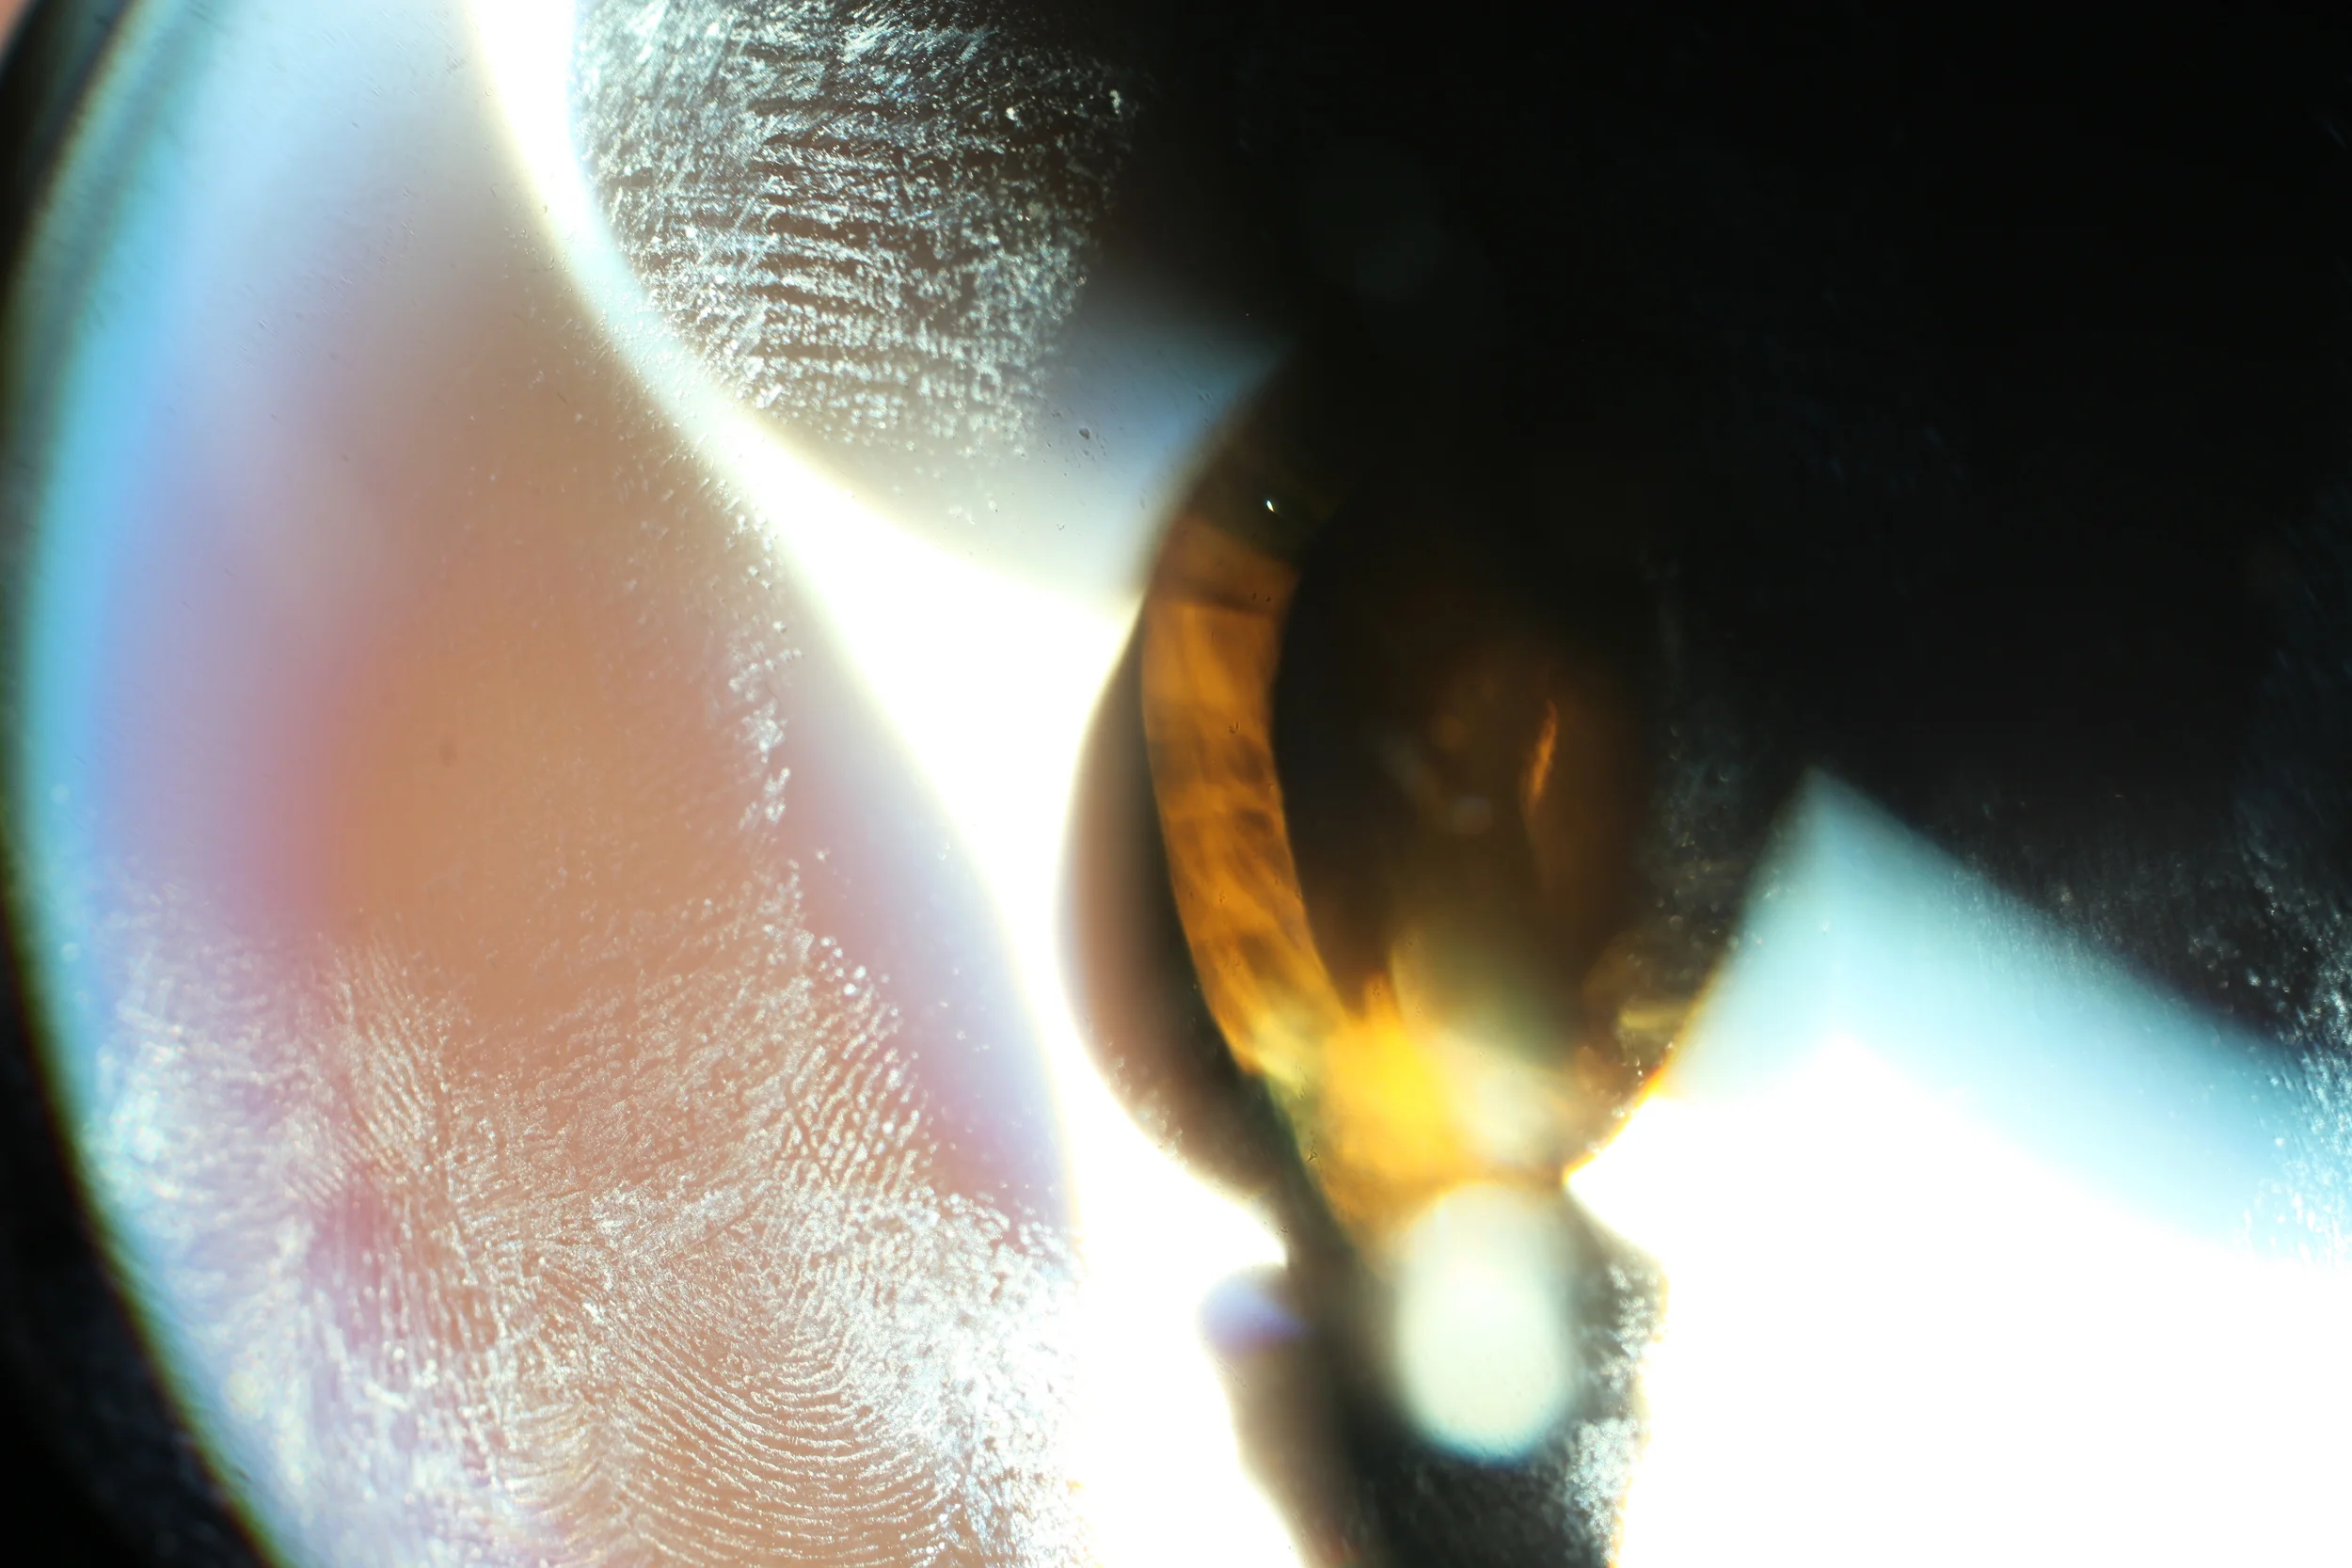

biotic